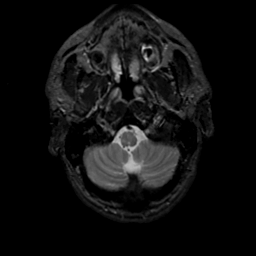

MR Study #13, May 19, 1991 -- Slice #5

[Home][Help][Clinical][Tour 1][Tour 2] Slice 5